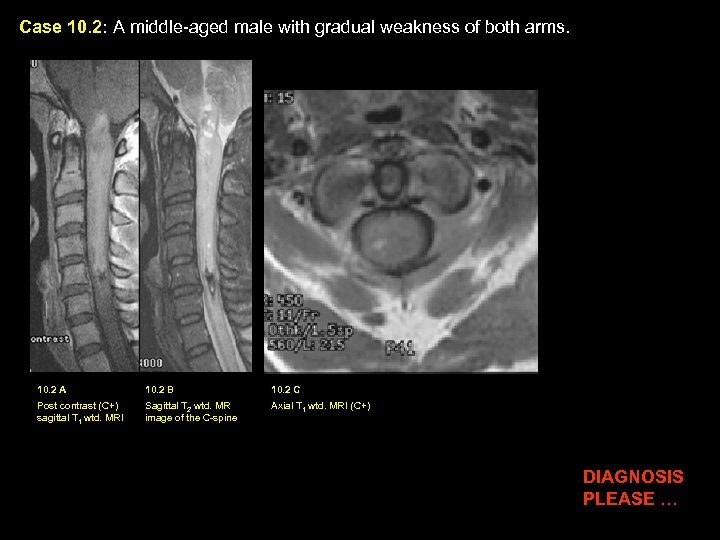

Case 10. 2: A middle-aged male with gradual weakness of both arms. 10. 2 A 10. 2 B 10. 2 C Post contrast (C+) sagittal T 1 wtd. MRI Sagittal T 2 wtd. MR image of the C-spine Axial T 1 wtd. MRI (C+) DIAGNOSIS PLEASE …

Case 10. 2: A middle-aged male with gradual weakness of both arms. Diagnosis: Ependymoma 10. 2 A 10. 2 B 10. 2 C Post contrast (C+) sagittal T 1 wtd. MRI Sagittal T 2 wtd. MR image of the C-spine Axial T 1 wtd. MRI (C+) Findings: : A sausage-shaped intensely enhancing tumor (yellow arrow in A) is seen within the upper cervical cord extending from just above the cranio-cervical junction with involvement of the dorsal medulla (black arrow in A) down to C 5 level. Small amount of old blood is better seen on T 2 wtd. image as an area of dark signal intensity within the tip of the tumor (white arrow in B). Central location of tumor (yellow arrows in C) is better appreciated on axial post contrast image.

Ependymoma of the Spinal Cord Incidence: Common intramedullary tumor in adults Pathology: Cellular tumors that originate from ependymal cells lining the central canal. Clinical Symptoms: Nuchal pain/radicular pain, Paresthesia, Motor weakness MRI Findings: Moderate to markedly enhancing tumor, Blood products from hemorrhage within the tumor is common, Tumor can also contain intrinsic cysts. Treatment: Surgery. Ependymoma have a well-defined cleavage plane between the tumor and adjacent spinal cord. Thus, the tumor can be completely resected with modern neurosurgical techniques with relief of clinical symptomatology. Recurrence is rare following complete resection.